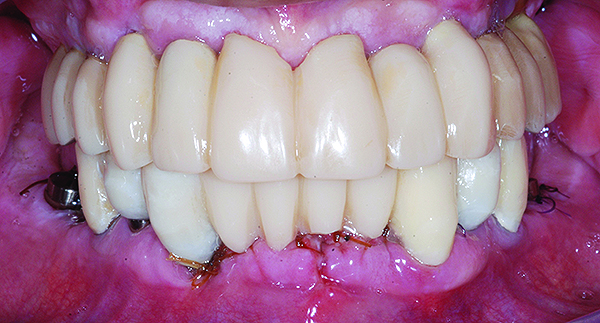

Fig 15. Intraoral frontal view of completed maxillary and mandibular zirconia restorations.

Figure 15

The maxillary prototype was adjusted, polished, and left to function with the mandibular provisional. The definitive maxillary zirconia restoration was then completed from the information provided by the prototype, and the cutbacks for the facial porcelain (Nos. 6 through 11) were done after milling but before sintering. Subsequently, the mandibular prototype was adjusted to the sintered and colored maxillary zirconia framework before the application of porcelain to Nos. 6 through 11 and final glazing (Figure 11). Following this step, the mandibular definitive monolithic zirconia restoration was milled, colored, and sintered. The facial porcelain (Nos. 6 through 11) was applied, and then both maxillary and mandibular restorations were stained and glazed (Figure 12). Both bridges were inserted at the same time (Figure 13 through Figure 15). Minor occlusal adjustments and oral hygiene access was verified and the zirconia surfaces polished. The bridge screws were torqued to 20 Ncm according to the manufacturer’s recommendation, and No. 24 was luted with a provisional cement. Postoperative radiographs were taken (Figure 16).

The patient has been followed for continuing care since completion of the reconstruction and no complications have been reported to date (Figure 17 through Figure 20).